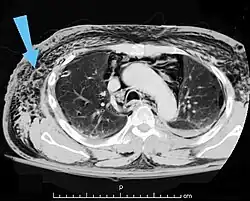

| An abdominal CT scan of a patient with subcutaneous emphysema (arrows) | |

Significant cases of subcutaneous emphysema are easy to diagnose because of the characteristic signs of the condition.[1] In some cases, the signs are subtle, making diagnosis more difficult.[13] Medical imaging is used to diagnose the condition or confirm a diagnosis made using clinical signs. On a chest radiograph, subcutaneous emphysema may be seen as radiolucent striations in the pattern expected from the pectoralis major muscle group. Air in the subcutaneous tissues may interfere with radiography of the chest, potentially obscuring serious conditions such as pneumothorax.[18] It can also reduce the effectiveness of chest ultrasound.[28] On the other hand, since subcutaneous emphysema may become apparent in chest X-rays before a pneumothorax does, its presence may be used to infer that of the latter injury.[13] Subcutaneous emphysema can also be seen in CT scans, with the air pockets appearing as dark areas. CT scanning is so sensitive that it commonly makes it possible to find the exact spot from which air is entering the soft tissues.[13] In 1944, M.T. Macklin and C.C. Macklin published further insights into the pathophysiology of spontaneous Macklin's Syndrome occurring as a result of a severe asthmatic attack.